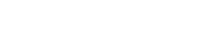

Il cuore dell’installazione è costituito da 260 sculture in ceramica che rappresentano cellule cerebrali: tante quante le persone che muoiono di fame in 15 minuti, il tempo di un pasto veloce, di una pausa tra riunioni o di una visita a una mostra. Utilizzando la risonanza magnetica funzionale, l’artista ha analizzato la propria attività cerebrale stimolata dalla fame, elaborando modelli tridimensionali, realizzati con la stampa 3D e poi trasformati in sculture in ceramica. Le sculture poggiano su piastrelle realizzate a mano che rappresentano sezioni del cervello dell’artista, evocando il collasso sociale delle disuguaglianze. Su uno schermo appare il conteggio delle vittime della fame, vite ridotte a numeri, mentre da “Part One” — prima parte del film World of Plenty, presentata in anteprima — si sente il cadere di gocce che scandisce il tempo. “World of Plenty” fonde così esperienza personale e collettiva e invita a passare dalla percezione individuale alla consapevolezza comune, rendendo impossibile ignorare la crisi della fame.